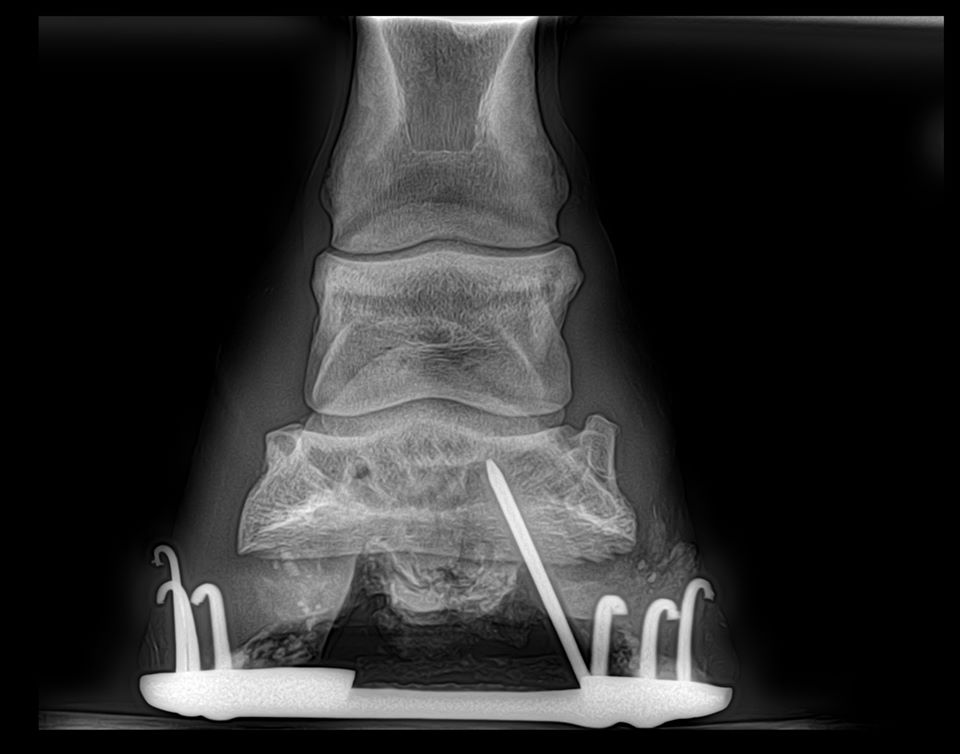

Nail embedded in hoof Equine Vet Centre Doncaster Nail In Foot Horse Posted by world equine veterinary association. A vet from rossdales veterinary surgeons in newmarket explains how to prevent further damage and ensure. Someone said i should have left it in until the vet or farrier. My horse had a nail in the bottom of his foot, and i pulled it out. Objects penetrating the hoof can. One practitioner outlines the. Nail In Foot Horse.

Lameness and the Embedded Nail Martin Godwin Equine Services Nail In Foot Horse Make the call, right away. a nail in the foot is a potentially life threatening condition and it’s important to know what to do if it happens to your horse. Susan kauffmann | january 28, 2020. Posted by world equine veterinary association. hoof punctures are common and almost always emergencies (and, it seems, rarely does a horse’s sole. Nail In Foot Horse.